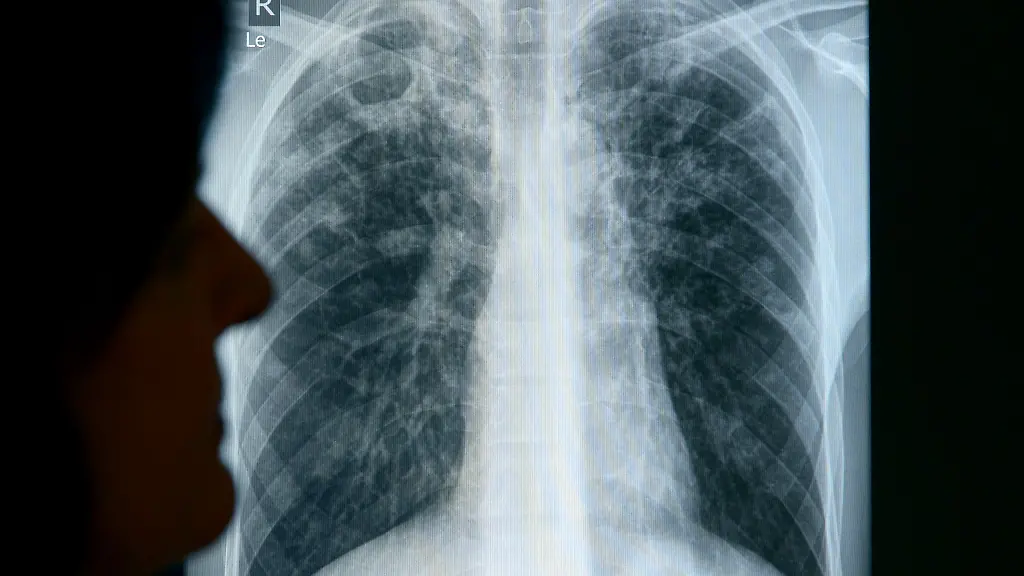

Tuberkulose ist eine schwerwiegende, ansteckende Infektionskrankheit, welche durch Bakterien verursacht wird. Tuberkulose verbreitet sich durch Tröpfcheninfektion in der Luft. Häufig geschieht dies durch Husten. Bei Kindern besteht die Gefahr schwerer Krankheitsverläufe, jedoch sind Kinder unter zehn Jahren aufgrund eines schwächeren Hustens in der Regel nicht so ansteckend wie Erwachsene.